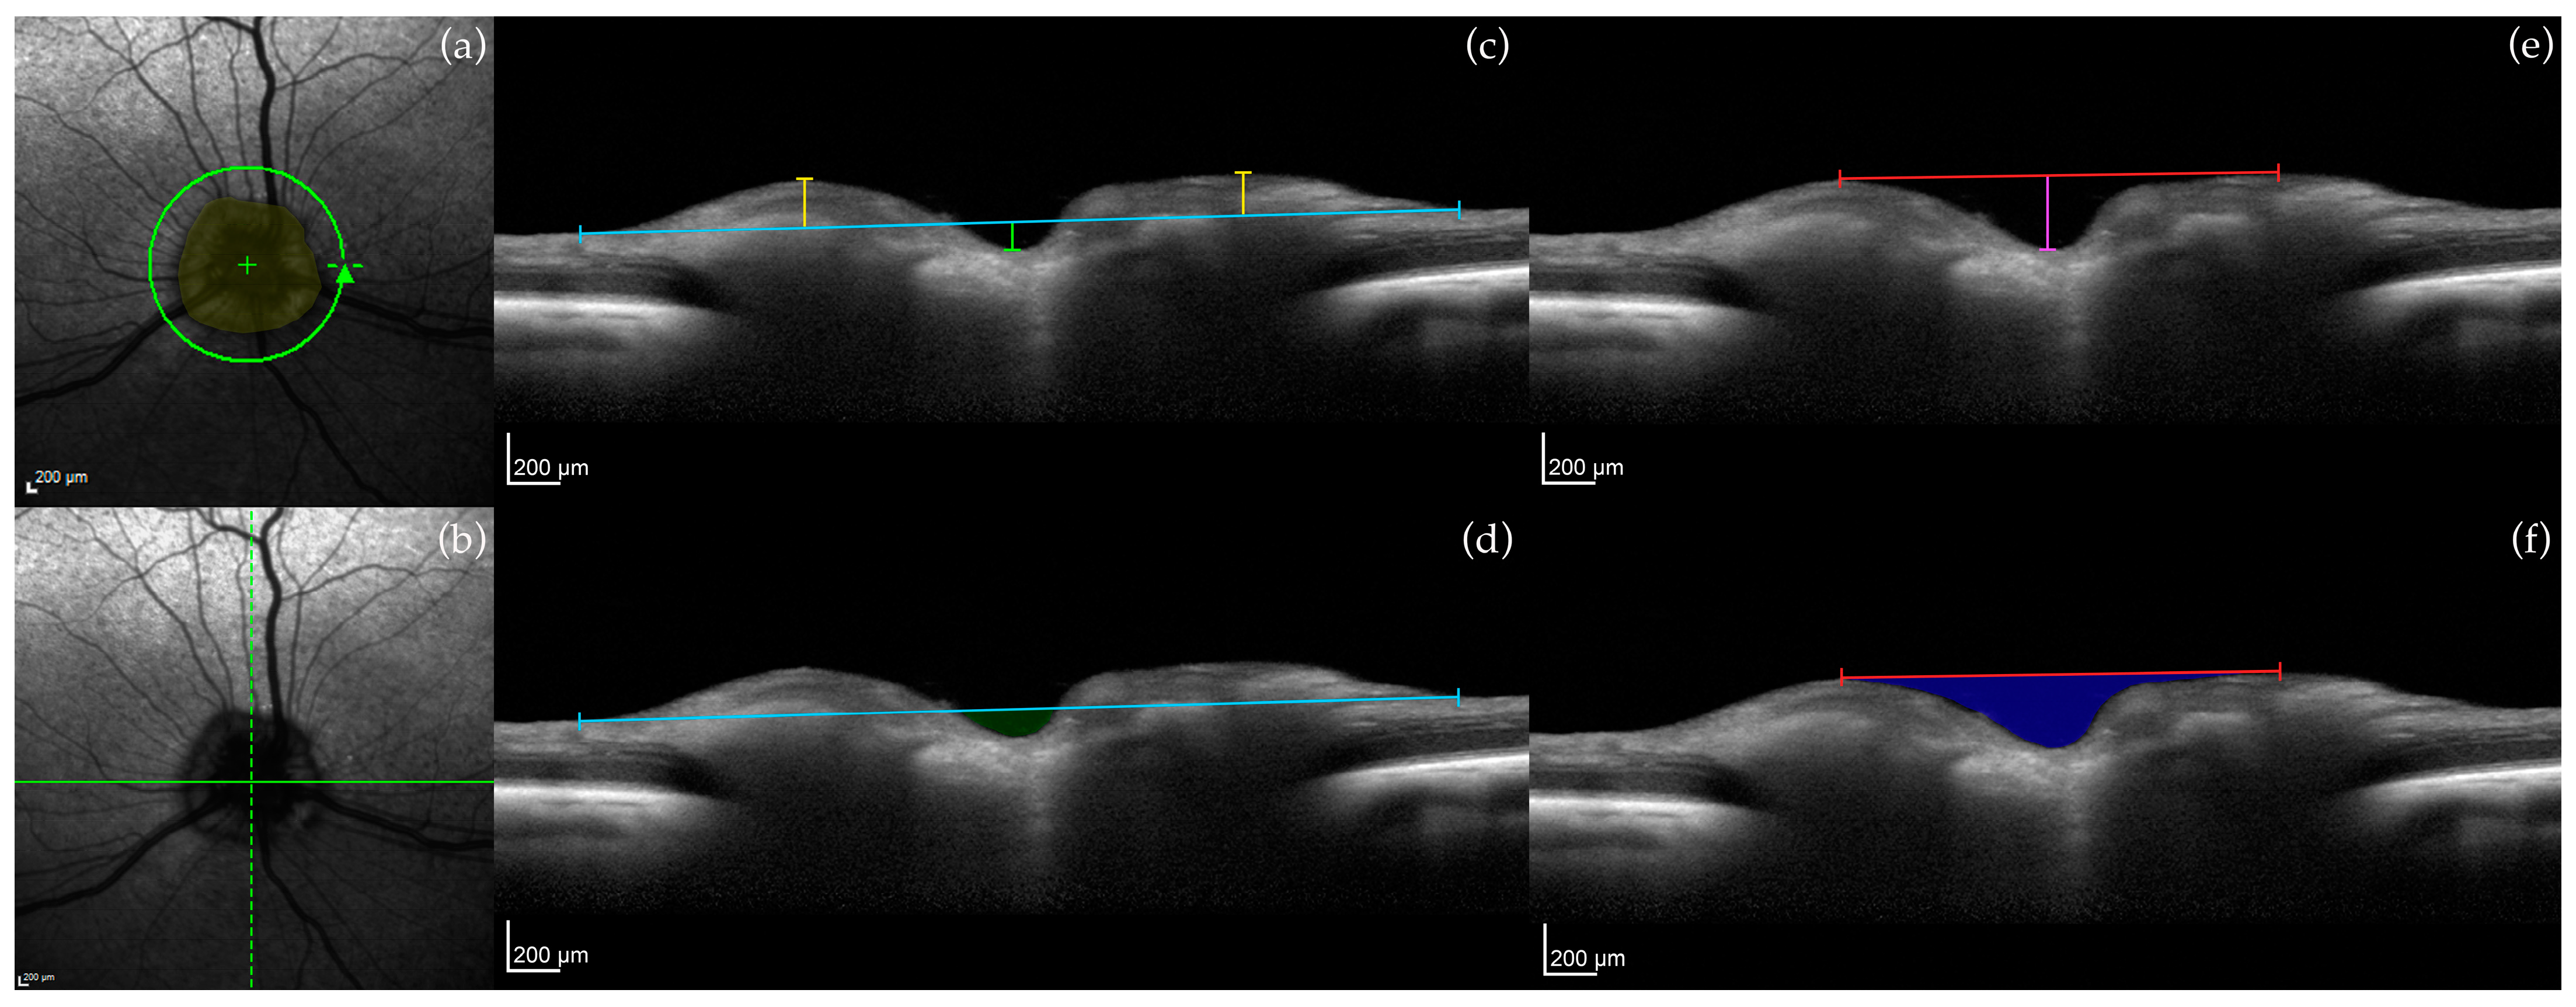

2.3.1. Optic Nerve Head (ONH) Measurements

2.3.2. Retinal Layer Measurements

3.1. Optic Nerve Head

3.2. Retinal Layers